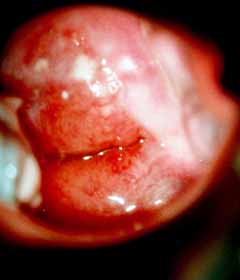

Κολποσκοπικές εικονες για τις αναγκες του forum.